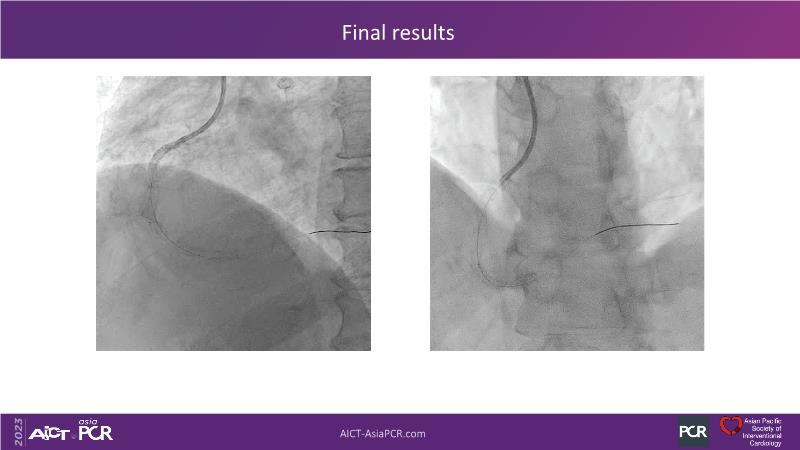

Leave nothing behind: DCB-only PCI strategy - How DCB evidence has changed today's practice?

This session offers an opportunity to stay informed about the recent developments in the International DCB Consensus Group, gain insights into the latest clinical data and real-world experiences related to drug-coated balloon (DCB)-only PCI, understand the safety aspects of DCB in managing complex PCI cases, and participate in an interactive discussion with experts.